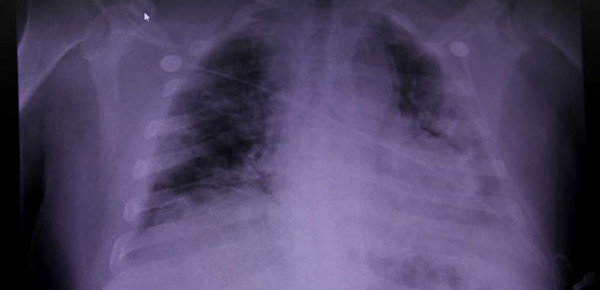

وكشفت النتائج أنه بعد ستة أسابيع من مغادرة المستشفى، لا يزال 88٪ من المرضى تظهر عليهم علامات تلف في الرئة في صور الأشعة المقطعية، وهي تشبه البقع على زجاج أرضي، و47٪ منهم يعانون من ضيق في التنفس، وفي 12 أسبوعا، كانت هذه الأرقام 56٪ و 39٪ على التوالي".

وقالت الطبيبة سابين ساهانيك من عيادة الجامعة في إنسبروك، وهي عضو ضمن الفريق الذي قام بالدراسة، إن "الناجين من كورونا يعانون من ضعف مستمر في الرئة بعد أسابيع من الشفاء".